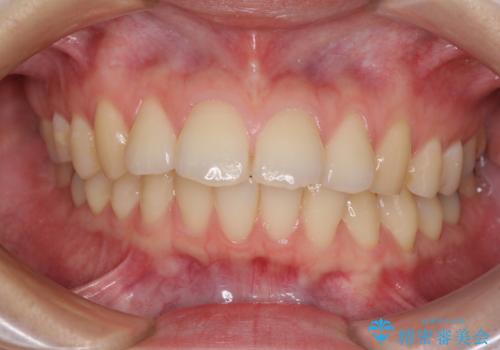

ご友人などがびっくりするほど口元の突出感を改善することができ、患者様には大変満足していただきました。